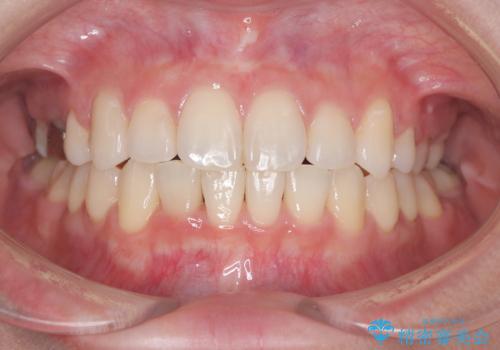

治療の途中で、1年間ご来院が難しい期間があり、当初の予定より治療期間は延長しましたが、

最終的には予定通りインプラントを使用せずに欠損部を閉鎖し、咬合も安定させることができました。